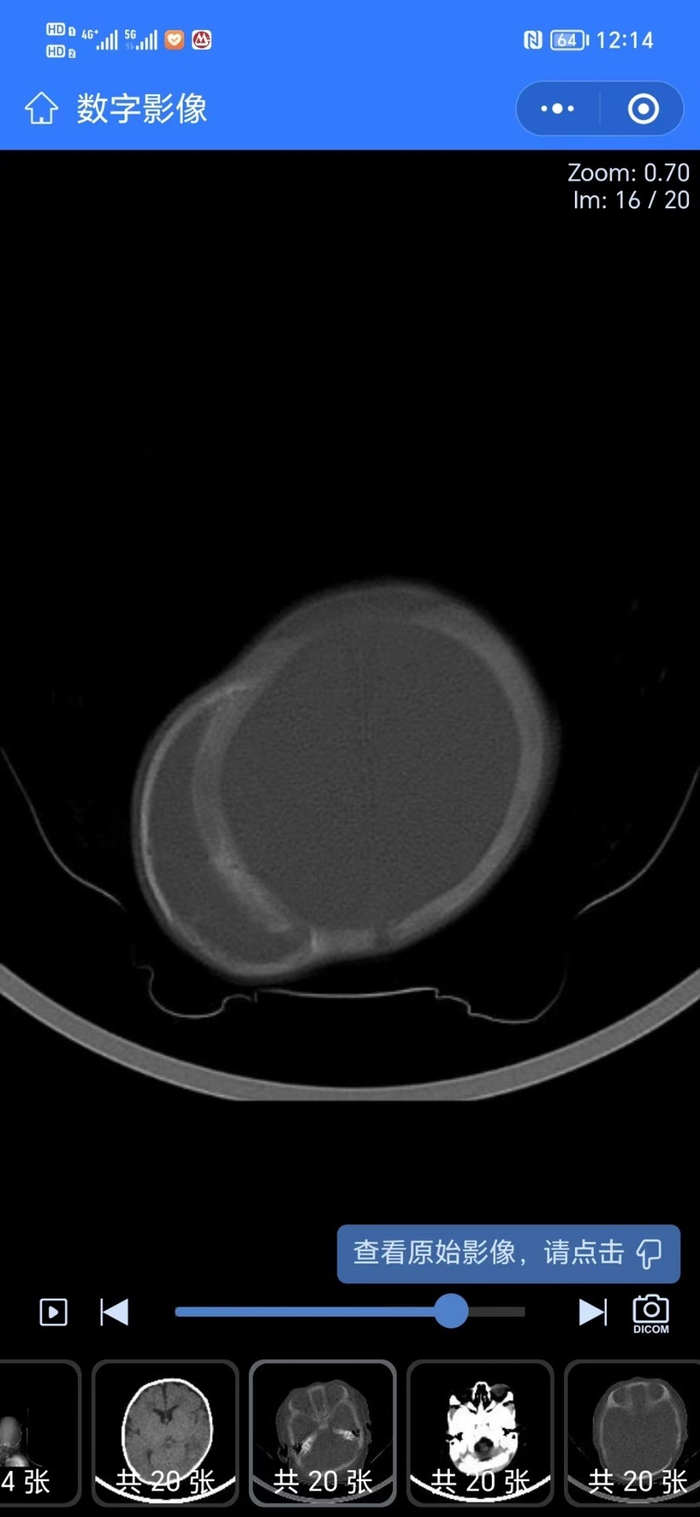

钙化的新生儿头皮血肿分两种类型,第1种类型如下图左,钙化血肿内层和颅骨轮廓一致,如果钙化范围小,可保守观察,随着后期颅骨自身生长塑形,外观可基本恢复正常。但如果范围广,外观畸形明显,则需全麻手术行外层钙化骨质磨除。第2种钙化类型如下图右,钙化血肿内层严重侵蚀下方的自身正常颅盖骨,需要全麻做畸形颅骨矫正修复手术。